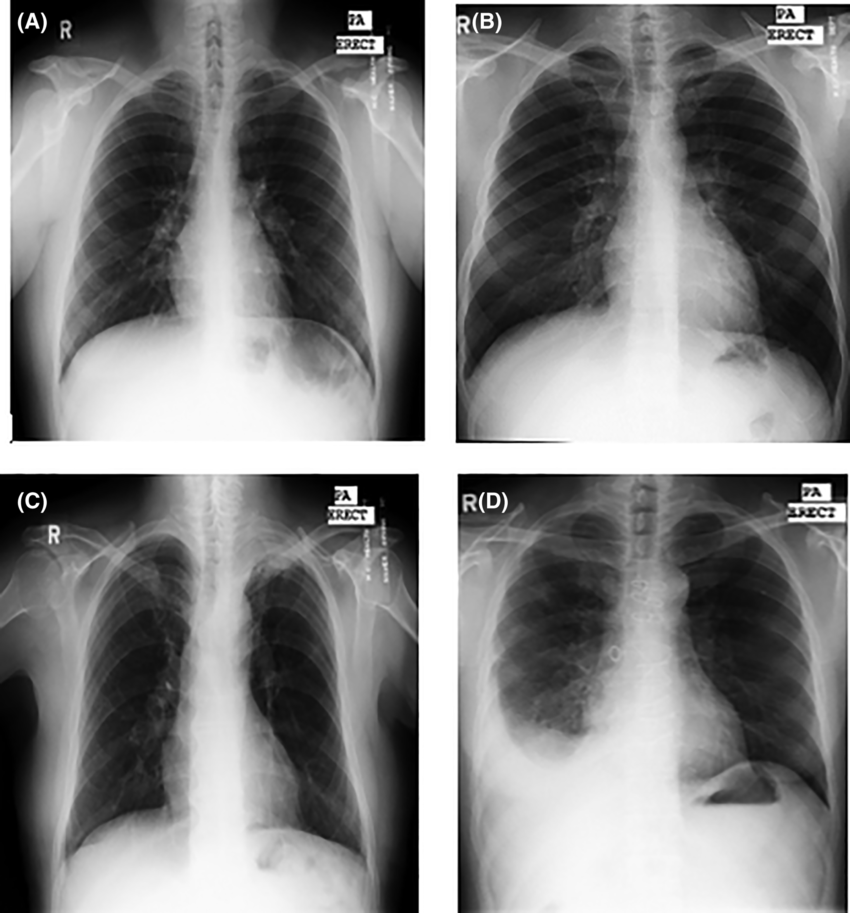

Chest X-Ray

A chest X-ray is a quick, non-invasive imaging test used to evaluate the lungs, airways, heart, and surrounding structures. It is commonly performed to assess conditions such as infections, fluid around the lungs, lung collapse, chronic lung disease, or changes in symptoms over time. During the exam, you will be asked to stand or sit in front of the X-ray machine and briefly hold your breath while the images are taken. The test takes only a few minutes, involves minimal radiation exposure, and you can return to normal activities immediately afterward.